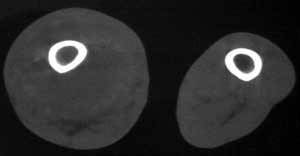

男56涨疼5-6月

右股骨下端包绕股骨见巨大软组织肿块,密度部俊,周围见瘤骨,下端骨皮质侵蚀变薄,骨质周围无骨膜反应, 考虑右股骨软骨肉瘤。

右股骨下段周围软组织肿块伴钙化,相邻股骨骨皮质受累,考虑软组织来源恶性病变

右股骨下段骨肉瘤,软组织内瘤骨,软组织肿块。